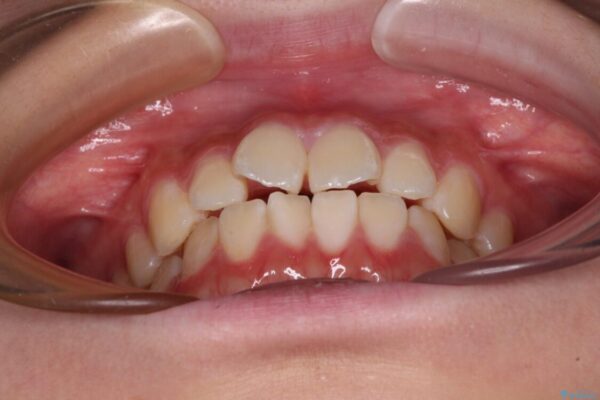

上下前歯のねじれを気にして来院された患者様です。

ワイヤー矯正でもマウスピース矯正でも対応可能でしたが、マウスピース矯正の自己管理が面倒であること、上顎前歯の捻転が著しいことから、ワイヤー矯正での治療を希望されました。

治療前

• インビザラインは使える自信がない ワイヤー装置にて矯正治療 治療前画像